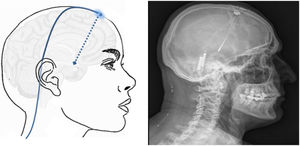

Technique. The procedure is performed on patients selected according to strict criteria.161 A stereotactic frame is fitted, and a head CT scan is performed to mark the stereotactic location of the hypothalamus. The CT images are combined with the previous MRI study in the neuronavigation system to identify the best entry point and trajectory to guide the electrode to the target. The electrode is inserted through a frontal burr hole (Fig. 7) and subcutaneous tunnelling is performed to run the lead from the burr hole to the subclavicular or periumbilical area where the generator will be implanted.